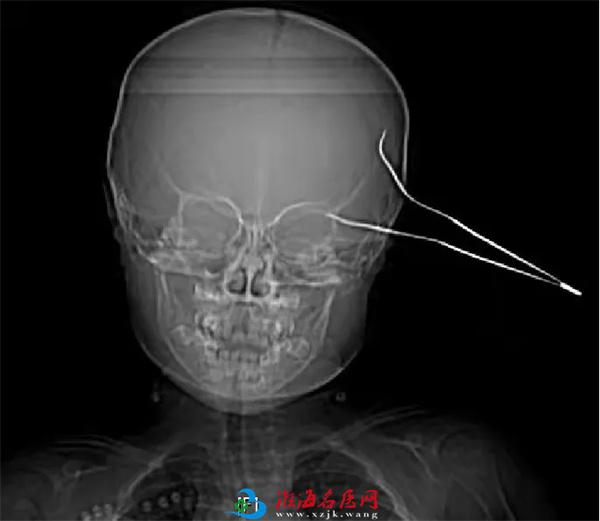

患儿笑笑(化名)是一位天真活泼,率真可爱的女孩,在父母的呵护下快乐成长。然而,天有不测风云,2021年10月23日中午10时许,笑笑在玩闹过程中不慎摔伤,致15cm长的金属镊子刺入头部,当时伤口少量出血,笑笑因疼痛哭闹不止,家人将笑笑紧急送至当地医院,头颅CT示左侧颞部条状致密影穿透左侧颞骨,深入左侧颞叶,情况十分危急,当地医院建议转至徐医附院进行手术治疗。

医院急诊医护人员接诊后,立即联系神经外科值班医生进行会诊。神经外科医师张桐会诊发现,笑笑左侧颞部金属质镊子两支齿的尖端均深入皮下,余在外的镊子底部已经严重弯曲变形,由此可见患儿受伤时所受外力之大。张桐医师查阅CT后立即向凌南主治医师及刘勇主任医师紧急汇报。刘勇主任团队经过综合讨论和全面评估,认为需要立刻进行手术,取出脑部异物,以免引发二次伤害和颅内感染,于是,快速启动医院绿色救治通道、与患儿家长沟通、联系手术室进行术前准备、联合多学科进行保障……一场与死神的赛跑正式开启。

回忆起那天的情景,刘勇主任依旧历历在目,因为刺破颞骨的镊子一端已刺破硬脑膜,刺穿大脑颞叶皮层,镊子尖部直逼侧裂大血管,万幸的是,镊子尖并没有刺破大脑中动脉和重要静脉。参与手术的王雷副主任医师说:“刘主任经常教导我们年轻医生说,外科医生遇事心要静,手要稳,脑外科医生尤其如此,心和手都要稳如泰山。的确这个小女孩受伤的地方太危险,太考验医生的心理素质和专业技术水平了。”刘勇主任补充说:“看着小女孩稚嫩可爱的小脸蛋,想着她以后如花般灿烂的人生,我们所有手术台上的医务人员就一个想法,就是尽自己最大的努力,确保手术成功!”